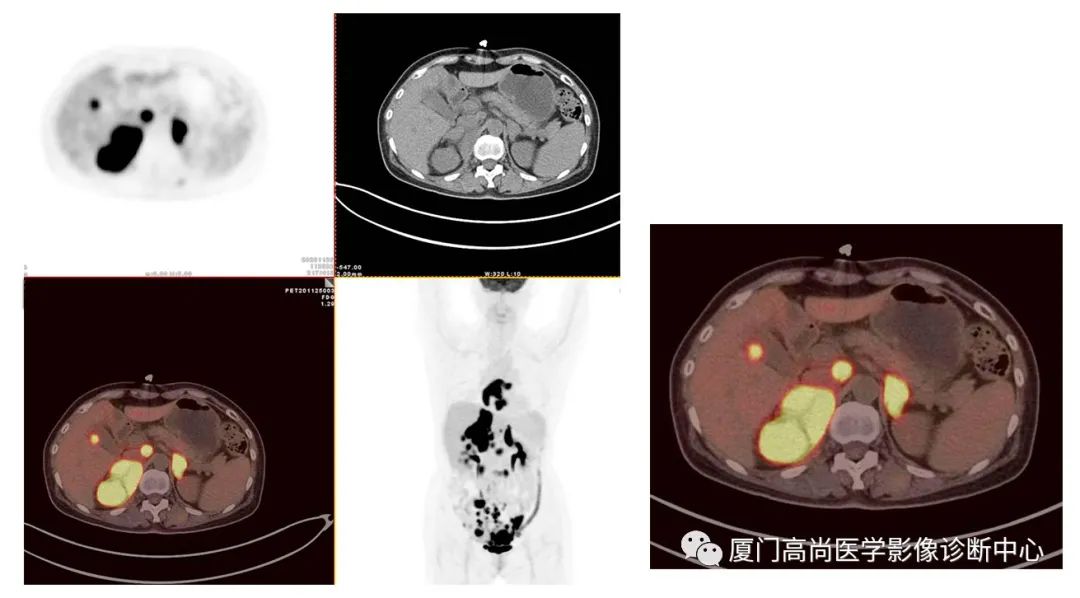

雙側(cè)腎上腺病灶、膽囊病灶

腹腔淋巴結(jié)腫大

小腸多段淋巴瘤病灶

PET/CT發(fā)現(xiàn) :左心房、右心房見團(tuán)塊狀FDG攝取增高;雙側(cè)腎上腺增大,F(xiàn)DG攝取增高;膽囊和胃壁結(jié)節(jié)樣FDG攝取增高;小腸多節(jié)段腸壁增厚,F(xiàn)DG攝取增高;腹膜后、腹腔及盆腔多發(fā)淋巴結(jié)腫大,F(xiàn)DG攝取增高;上述考慮為淋巴瘤

經(jīng)腎上腺穿刺活檢 :病理證實(shí)為彌漫大B細(xì)胞淋巴瘤